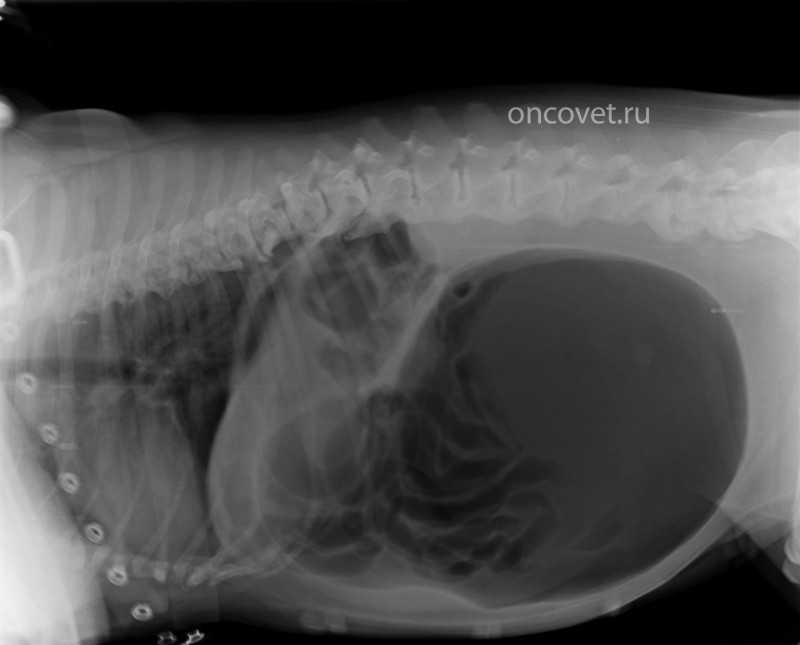

Диагностика непроходимости кишечника у собак

При подозрении на кишечную непроходимость после врачебного осмотра необходимо сделать рентгеновские снимки брюшной полости, желательно — в двух проекциях, т.е. снимок в положении на боку и в положении на спине. Поскольку на рентгеновских снимках мы видим двумерную картинку — тень от объемного (трехмерного) тела животного, то контуры разных органов накладываются друг на друга, и только сделав снимки в двух проекциях, бывает возможно понять, где локализуются те или иные структуры, видимые на снимке. На этих снимках можно увидеть рентгеноконтрастные вещества, плотность которых значительно превышает плотность мягких тканей организма и рентгенопрозрачные очаги, как правило — очаги газообразования, плотность которых наоборот, значительно ниже плотности мягких тканей.

Кроме того, на рентгеновских снимках можно увидеть признаки перитонита — воспаления серозных оболочек брюшной полости с выпотом жидкости. Такая находка в сочетании с признаками кишечной непроходимости, как правило, говорит о возможном прободении кишечника и о необходимости срочной операции.

Значительные очаги газообразования в кишечнике могут быть косвенными признаками кишечной непроходимости. Однако, косвенные признаки требуют верификации (подтверждения) диагноза. Поскольку речь идет о необходимости хирургической операции, и врач и владелец всегда хотят максимальной определенности.

В тех случаях, когда простое рентгеновское исследование не дает нам ясного понимания проблемы, следующим этапом диагностики становится рентгеновское исследование с контрастом. В качестве контрастного вещества используется сульфат бария, белый порошок без вкуса и запаха (как мел), который не всасывается из желудочно-кишечного тракта, а на рентгеновских снимках виден ярким белым (контрастным) пятном. Сульфат бария подмешивается в кефир и выпаивается животному. Как правило, это приходится делать насильно. Предварительно необходимо сделать пациенту противорвотный укол для того, чтобы исследование не завершилось, не успев начаться.

Поролон, пропитанный сульфатом бария в желудке хорька

После дачи контраста, делают серию рентгеновских снимков с определенными временными промежутками, оценивая прохождение содержимого по желудочно-кишечному тракту. И если содержимое не проходит за определенное время до прямой кишки, это нам позволяет диагностировать кишечную непроходимость и предлагать в качестве единственного эффективного варианта лечения операцию.